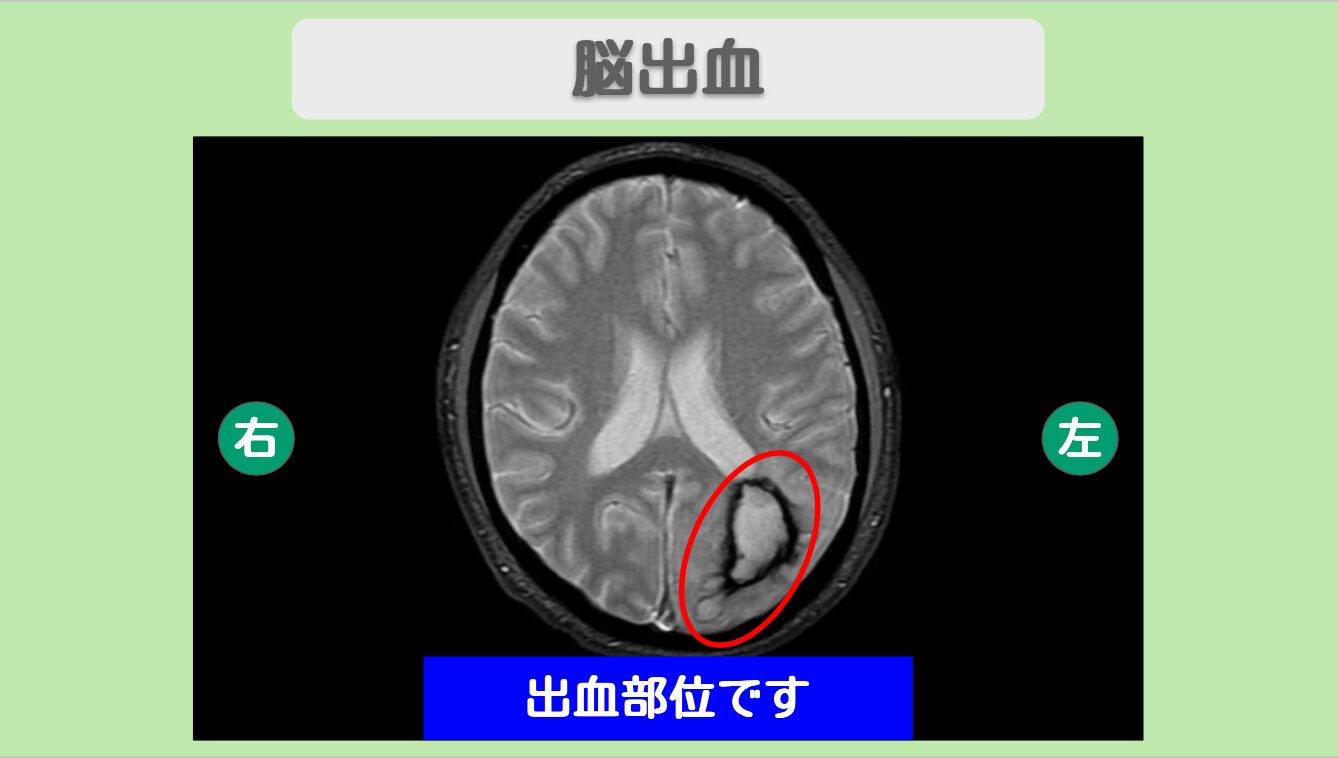

MRI所見

MRIにて左後頭葉に出血部位を認めます。